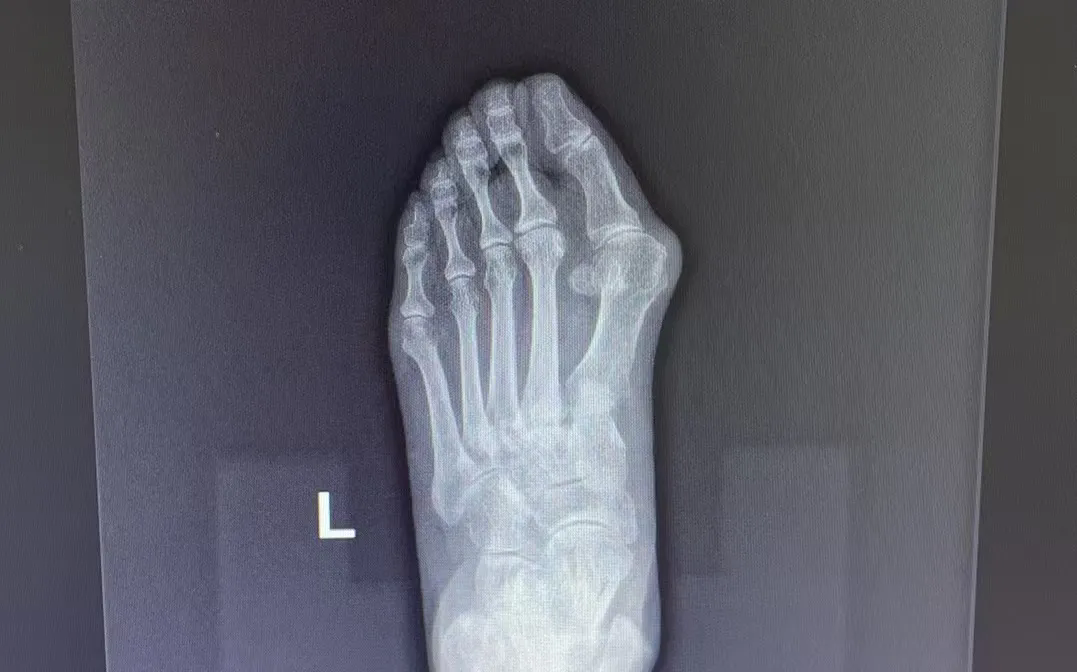

拇指外翻

这一复杂的解剖畸形

不仅影响美观

更会带来红肿疼痛、关节炎等症状

严重干扰日常生活

尤其在中老年女性群体中

拇指外翻的发病率较高

给生活质量带来了极大的困扰